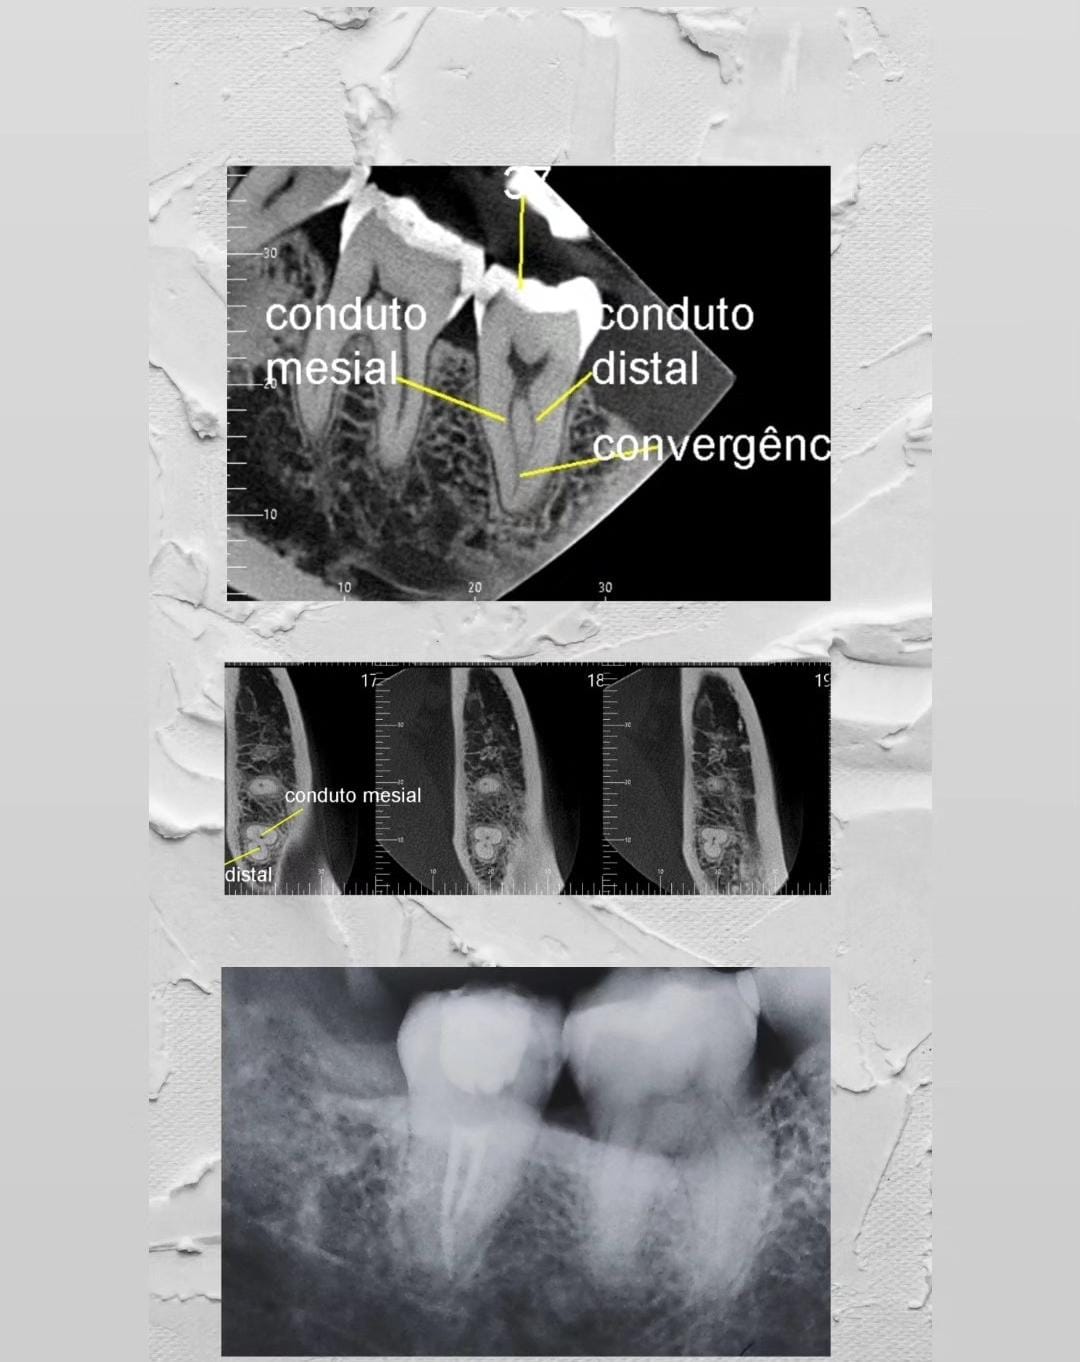

Especialidade principal. Remoção da polpa inflamada para alívio imediato da dor e preservação do dente.